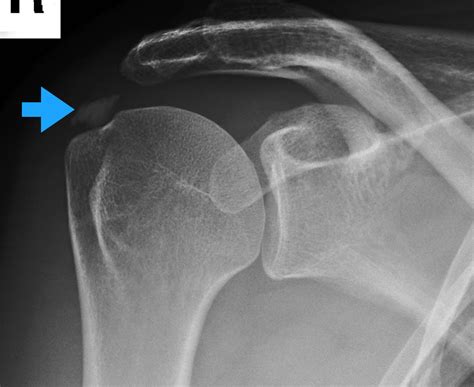

• Imaging tests: X-rays, ultrasound, or MRI scans can help visualize the calcium deposits and assess the extent of the damage.